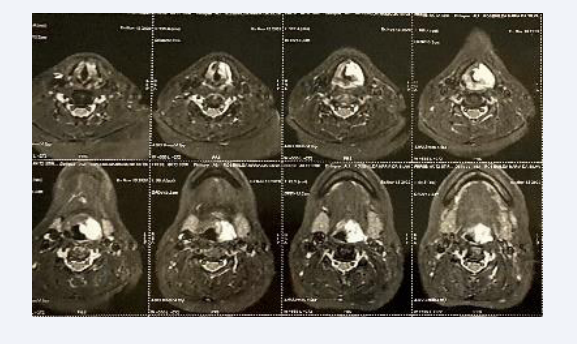

Axial MRI showing significant control after the third procedure

Figure 9: Axial MRI showing significant control after the third procedure

The control MRI after the third procedure presented the following report: “Tumor lesion with characteristics of residual and/or recurrent hemangioma. Trachea and infraglottic region without abnormalities (Figures 10,11).